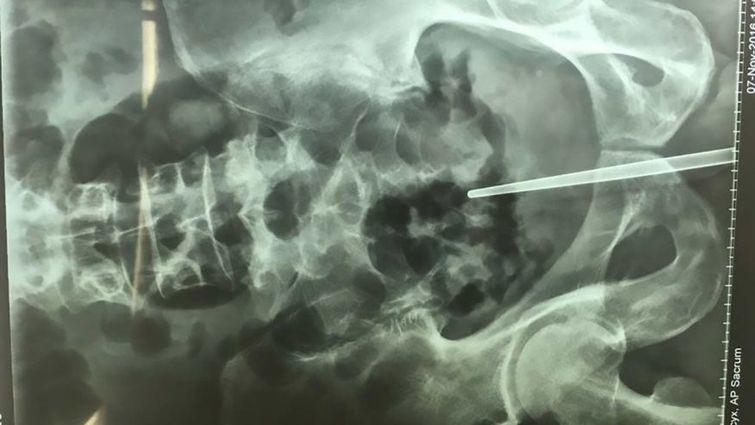

이 사건의 주인공은 중국 동부 저장성의 수도 항저우에 사는 첸이라는 남성. 그는 혈뇨의 원인을 알아보기 위해 스테인리스강으로 만든 7인치(약 18cm)의 젓가락을 생식기에 깊숙이 쑤셔 넣었다가 빼내지 못하는 바람에 병원으로 옮겨져 제거 수술을 받았다는 것.